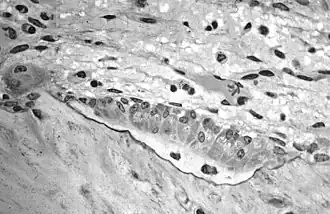

Osteoblasts actively synthesizing osteoid containing two osteocytes. -